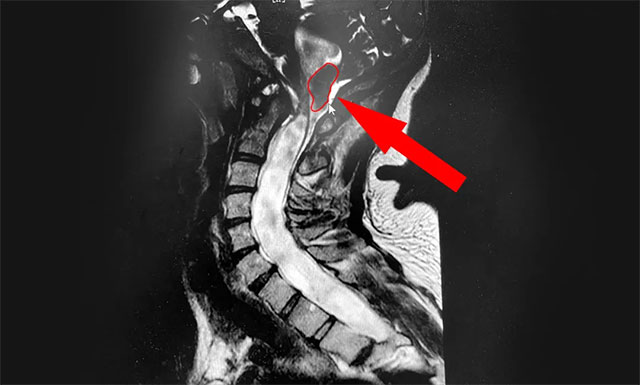

▲ MRI示患者小腦扁桃體下疝畸形

侯增欣主任耐心詢問了患者病史,并開展了有針對(duì)性的檢查。小潘的頸椎核磁檢查報(bào)告很快出來了,從影像上看,患者的頸6/7椎間盤確實(shí)稍有突出,但程度并不嚴(yán)重。而導(dǎo)致患者癥狀不斷加重的“元兇”同時(shí)現(xiàn)形:小腦扁桃體延長成楔形進(jìn)入了枕骨大孔及頸椎管,頸髓受壓水腫改變,頸髓及上端胸髓內(nèi)見條狀異常信號(hào),提示為“Chiari畸形伴脊髓空洞癥”。

侯主任解釋道,Chiari畸形,又稱為小腦扁桃體下疝畸形(Arnold-Chiari malformation,ACM),是因?yàn)楹箫B腦先天發(fā)育異常,小腦扁桃體向下延伸,壓迫腦干、脊髓而引起的一種疾病,是引起脊髓空洞癥的常見原因。這一類型的脊髓空洞癥患者可出現(xiàn)枕部頭痛(由咳嗽、噴嚏等引起)、頸肩部疼痛、小腦共濟(jì)失調(diào)表現(xiàn)、頭暈、聲音嘶啞、吞咽困難、睡眠障礙等一系列癥狀。